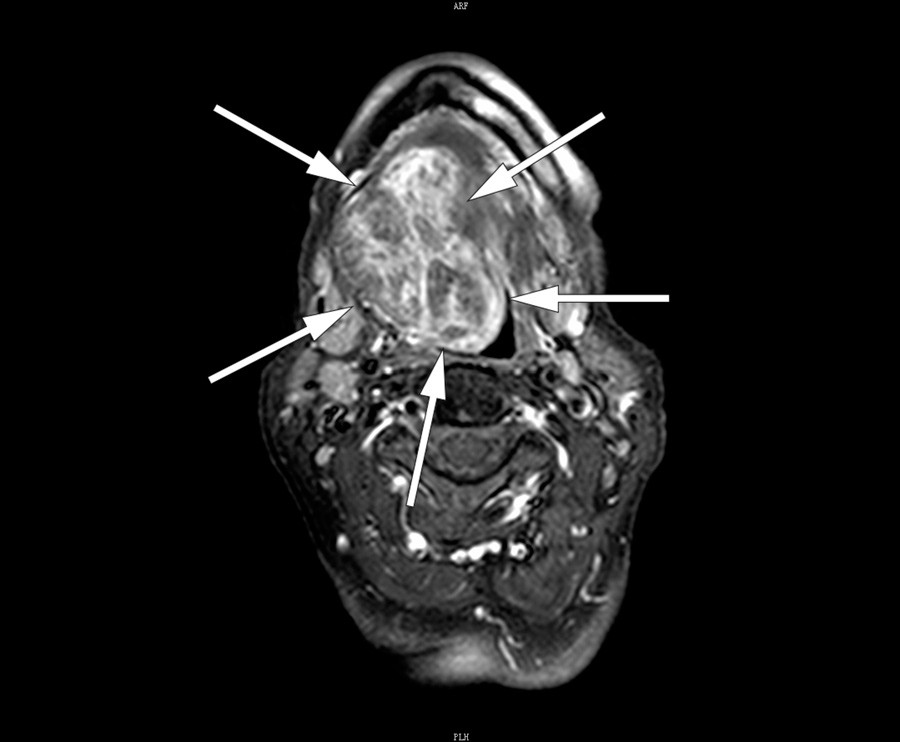

Det ble tatt CT collum med kontrast (bilde til venstre), som viste en stor tumor i munngulvet. MR collum med kontrast (bilde til høyre) viste uregelmessig kontrastopptak i tumor. Finnålscytologi viste vev best forenlig med glandula thyreoidea uten tegn til malignitet. Funnene tydet på ektopisk thyreoidea, og regranskning av CT-bildene viste manglende thyreoideavev på vanlig lokalisasjon. Blodprøver viste at pasienten var eutyreot og negativ for antityreoperoksidase og antityreoglobulin.